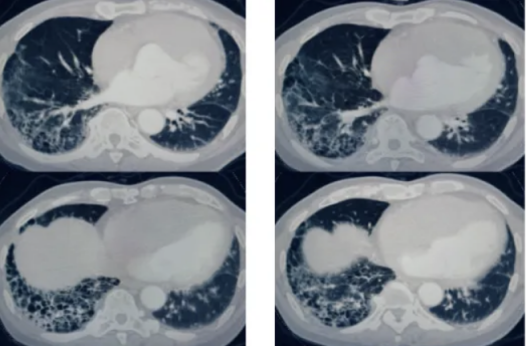

医生立即为病人安排了肺部CT检查,发现王大爷肺部已经出现明显的肺纤维化特征,更为严重的是,局部已经形成了蜂窝状的病变形态。